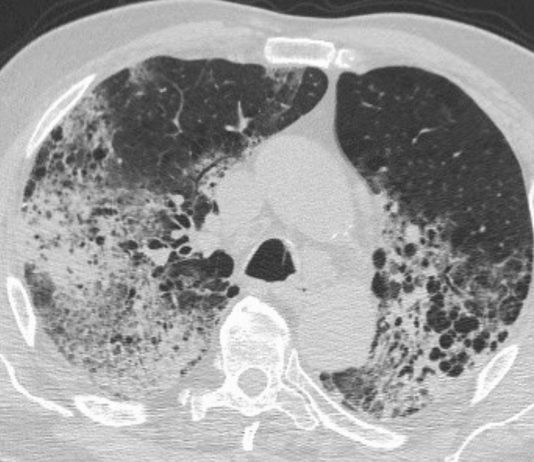

Paziente di 77 anni giunge per tosse e dispnea dal circa 5 giorni per cui ha assunto prima terapia con amoxicillina/ acido...

Paziente di 88 anni, maschio, accede al Pronto Soccorso del PO di Marcianise (direttore: Prof. M. Giordano) il 02/03/2020.